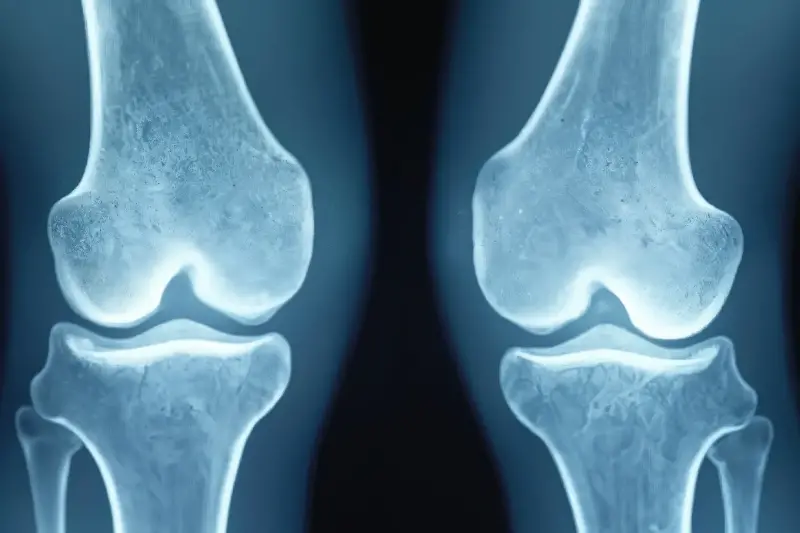

傳統意義上,我們的骨頭是身體最堅硬的組織,用來支撐體重與保護內臟,而這一切功能的發揮,都與「地球重力」息息相關。地球的重力讓我們每移動一步、行走、奔跑甚至靜止,都會對骨頭產生持續負荷,這促使骨骼細胞積極新陳代謝,分解舊骨、生成新骨,維持骨骼的健康與密度。

然而,在太空失重環境下,這一切都被打破。在「微重力」條件下,身體不再需要對抗重力,也就失去了維持骨頭堅韌與厚度的主要動力。醫學研究發現,宇航員短短在太空生活幾週至幾個月,就會明顯經歷「骨質流失」現象。科學家觀察到,宇航員每個月大約會失去0.5%到1.5%的骨密度,這個速度遠遠高於地球上因年齡或疾病造成的骨質疏鬆現象。長時間失重,甚至可能導致骨頭脆弱到輕微撞擊就骨折的嚴重後果。

那麼,失重下骨密度下降的過程是如何發生的呢?主要涉及到兩種骨細胞:「造骨細胞」與「蝕骨細胞」。自然狀況下,這兩者維持著精妙的平衡。造骨細胞負責組成新的骨質,而蝕骨細胞則分解舊骨細胞。當宇航員進入太空,微重力環境會讓蝕骨細胞活動加強,反而造骨細胞活性減弱,導致骨質大量流失、骨密度急劇下降。